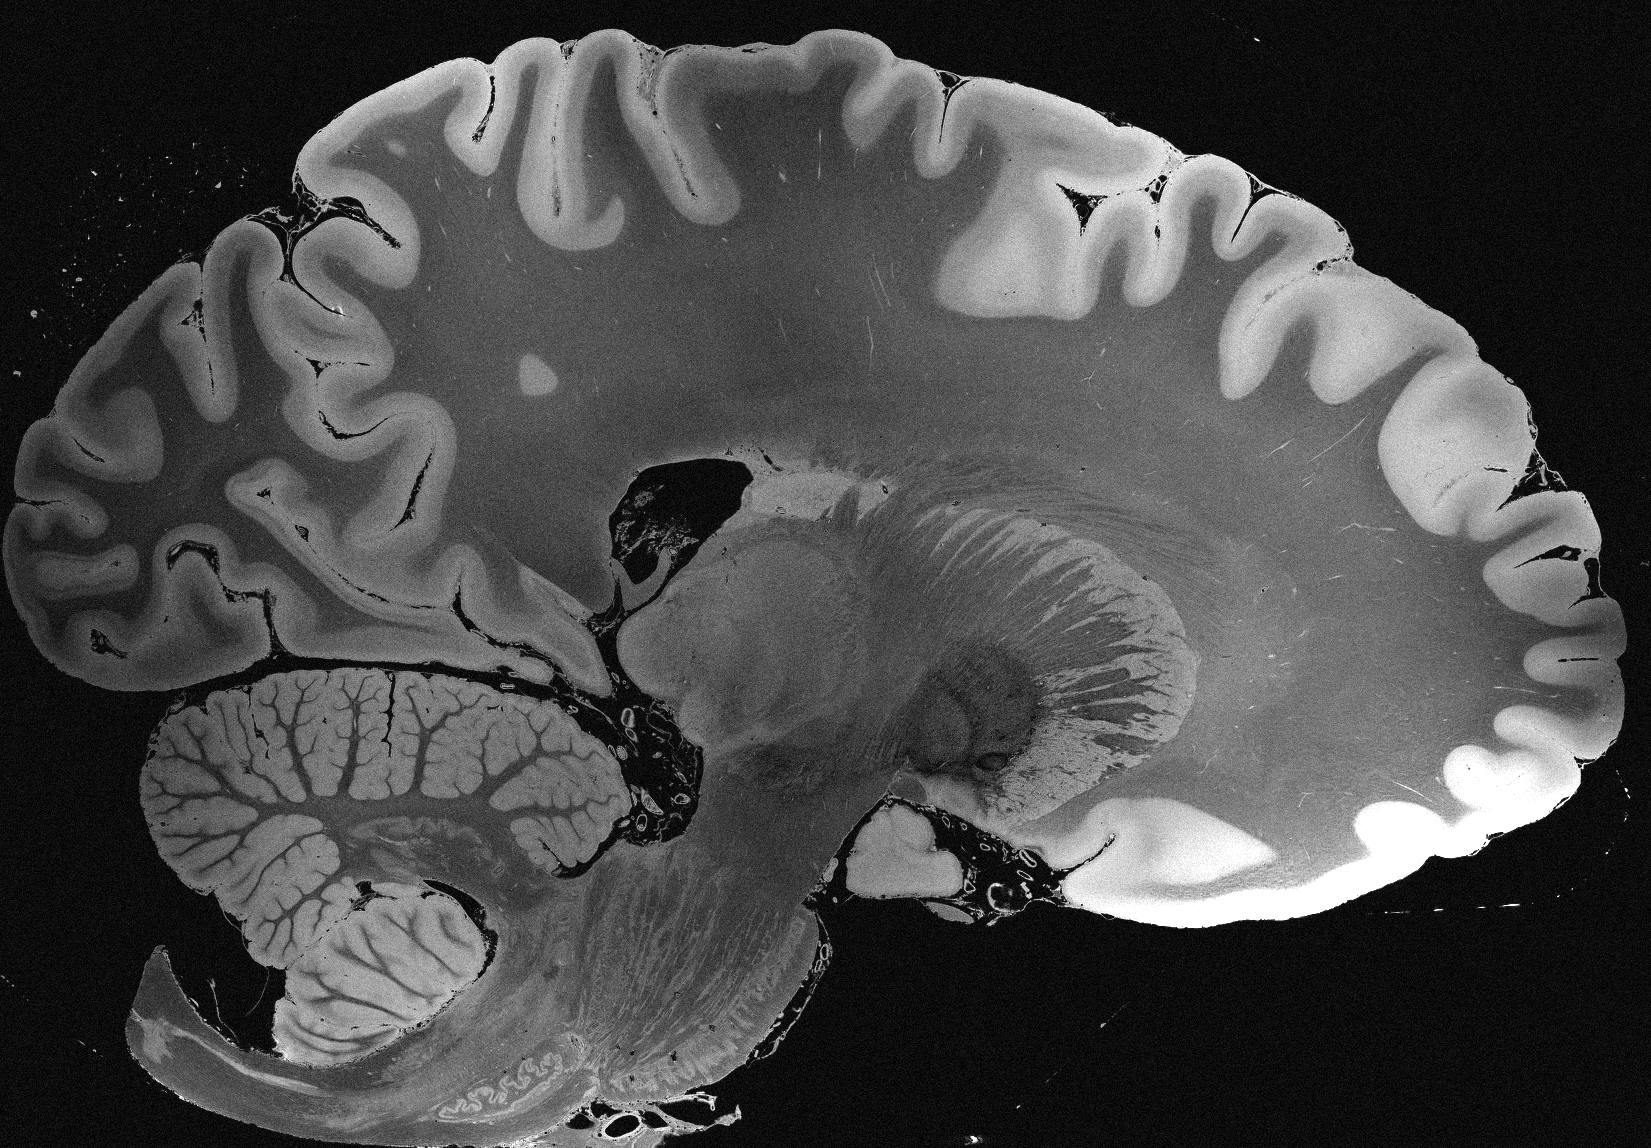

4.2 Registration to a 100 micron ex-vivo brain MRI volume

To showcase the efficacy of our method on real large scale images, we register a 250 in-vivo MRI image (Lüsebrink et al., 2017) to a 100 ex-vivo FLASH human brain volume (Edlow et al., 2019). This represents an inverse problem with more than 11.2B optimizable parameters (compared to 20M for clinical datasets), or 44.8GB of GPU memory. The entire problem does not fit on most GPUs, necessitating distributed multimodal registration. We optimize a composite transform - affine followed by a diffeomorphic mapping; details can be found in Section E.1. Multimodal deformable registration took 58 seconds on 8 NVIDIA A6000 GPUs, which is unprecedented at this resolution. Fig. 6 shows qualitative results, highlighting the ability to register highly detailed structures such as cerebellar white matter; these structures are not visible at macroscopic scales. The resultant advantages of performing registration at this scale can allow researchers to characterize the neuroanatomy at microscopic resolutions and allow morphometric analysis of cortical layers and subcortical nuclei among other structures.